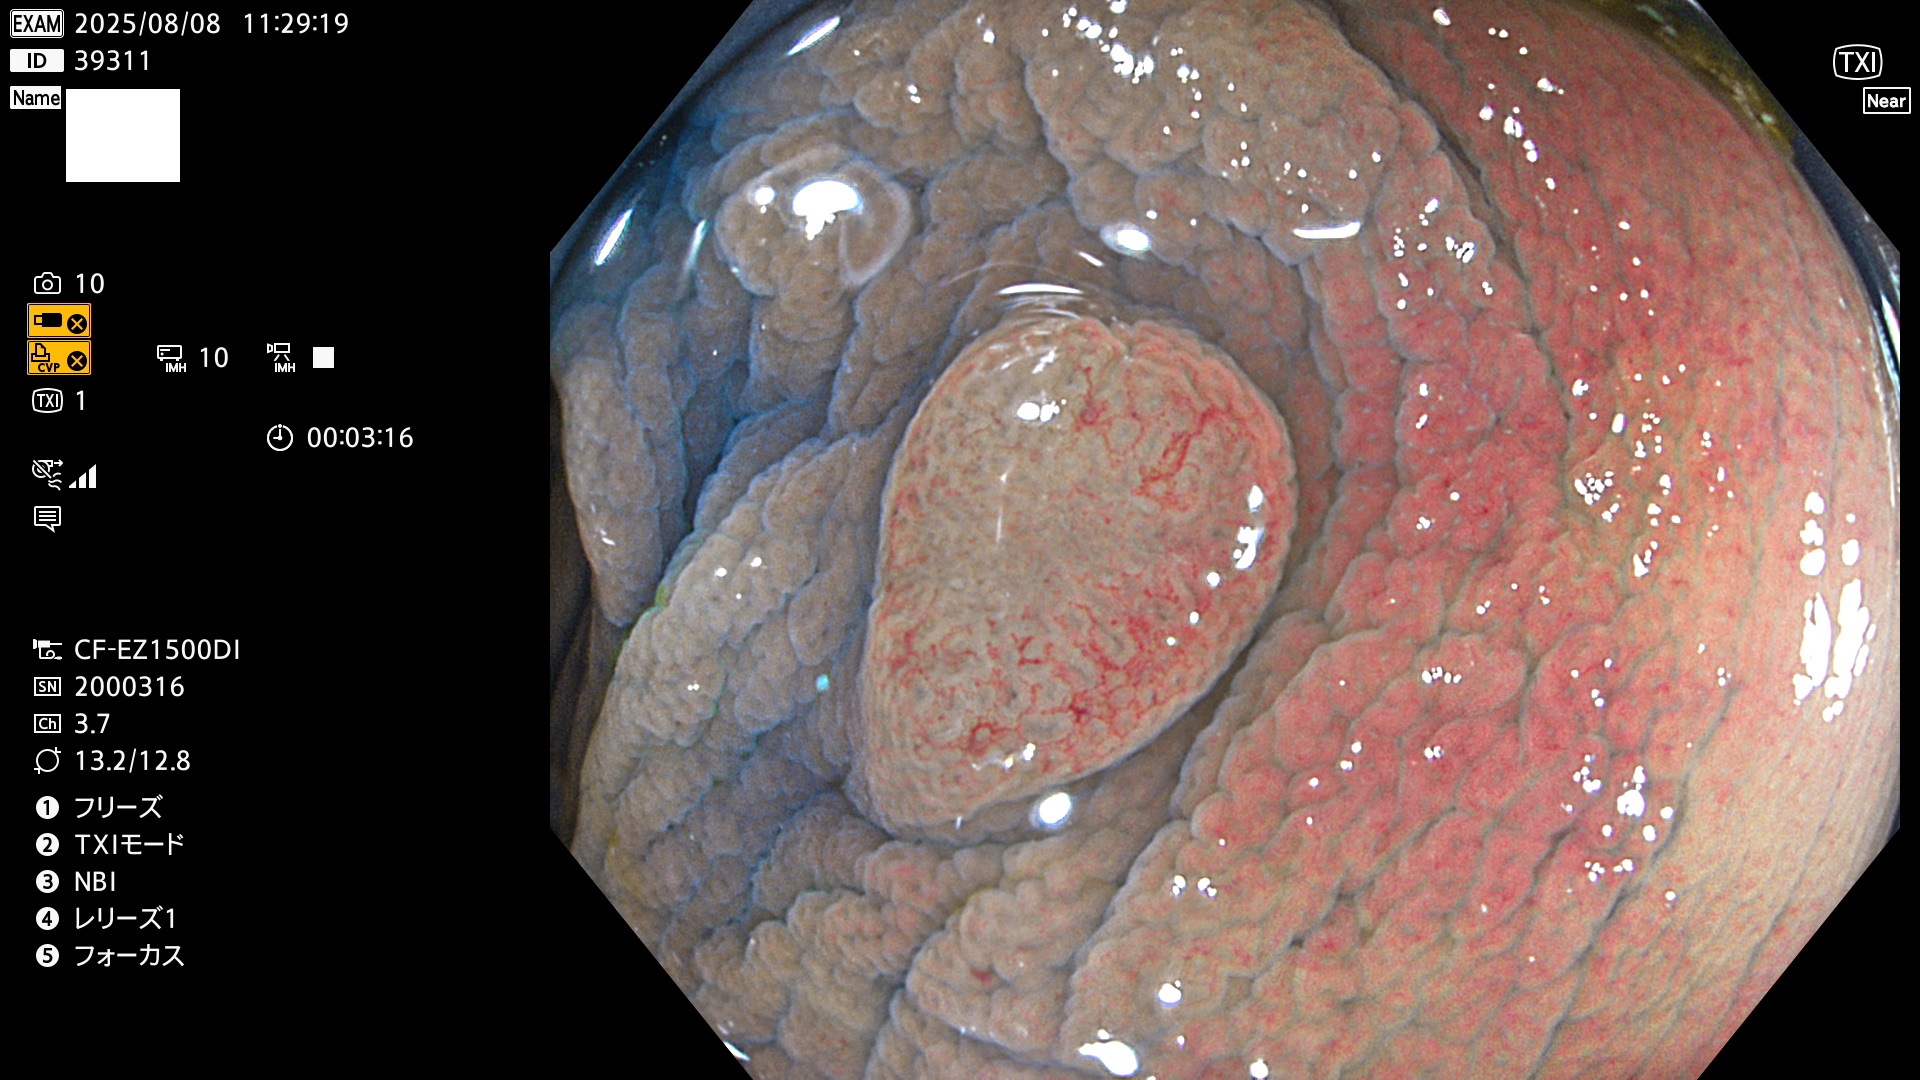

完全に平坦な物をUb、陥凹している物をUcと呼びます。Ubは認識が困難で、Ucはびらん(炎症)と紛らわしいために見落とされやすく、「内視鏡後・大腸癌」の原因になります。

毎週の検査(木・金・土・日)に発見されたUbとUc型・腺腫を、その週の日曜の夜にUPし1週間、提示します。

2025年8月7日〜8月10日の4日間(35件)6個 (Uc_ADR=6個/35人=17%)